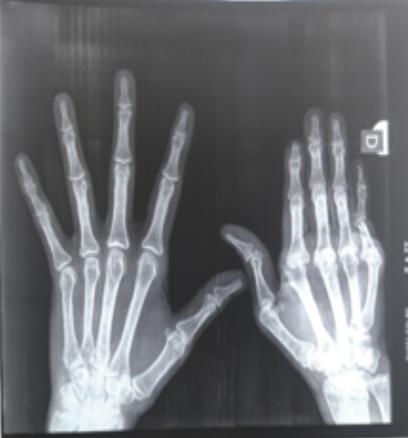

Une patiente âgée de 45 ans, sans antécédent particulier, droitière et ouvrière dans le domaine de la confection, souffre de déformations avancées de la main droite. Sa main gauche est normale. Les douleurs prédominent au niveau des articulations des deux mains de façon symétrique. Elle est suivie pour une polyarthrite rhumatoïde (PR) séropositive depuis vingt-deux ans, retenue selon les critères de l’ACR de 1987. Le facteur rhumatoïde et les anticorps anti-CCP étaient respectivement à 512 UI/L et 266,48 UI/L. Les anticorps antinucléaires (AAN) étaient négatifs. Sur le plan thérapeutique, la patiente a initialement reçu une corticothérapie à 20 mg/j associée à la chloroquine 200 mg/j pendant quatre ans. En l’absence de réponse thérapeutique et avec l’apparition des déformations de la main droite, le méthotrexate a été démarré à raison de 10 à 15 mg par semaine. Des déformations unilatérales de la main droite se sont installées progressivement, occasionnant une impotence fonctionnelle bien tolérée, réalisant un aspect typique de main rhumatoïde (fig. 1). Le poignet droit est mobile et indolore. La main gauche ne montre aucune déformation et les autres articulations sont libres et indolores. Radiologiquement, il existe des subluxations des métacarpo-phalangiennes (fig. 2). Les articulations interphalangiennes proximales et distales sont pincées, avec destruction de la tête de la phalange proximale du cinquième doigt. Les articulations intercarpiennes sont intactes. La main controlatérale n’a pas de lésions radiologiques avancées.

La patiente a ainsi des déformations unilatérales de la main droite, sans atteinte des os du carpe. Cette asymétrie constitue un aspect atypique au cours de la PR.